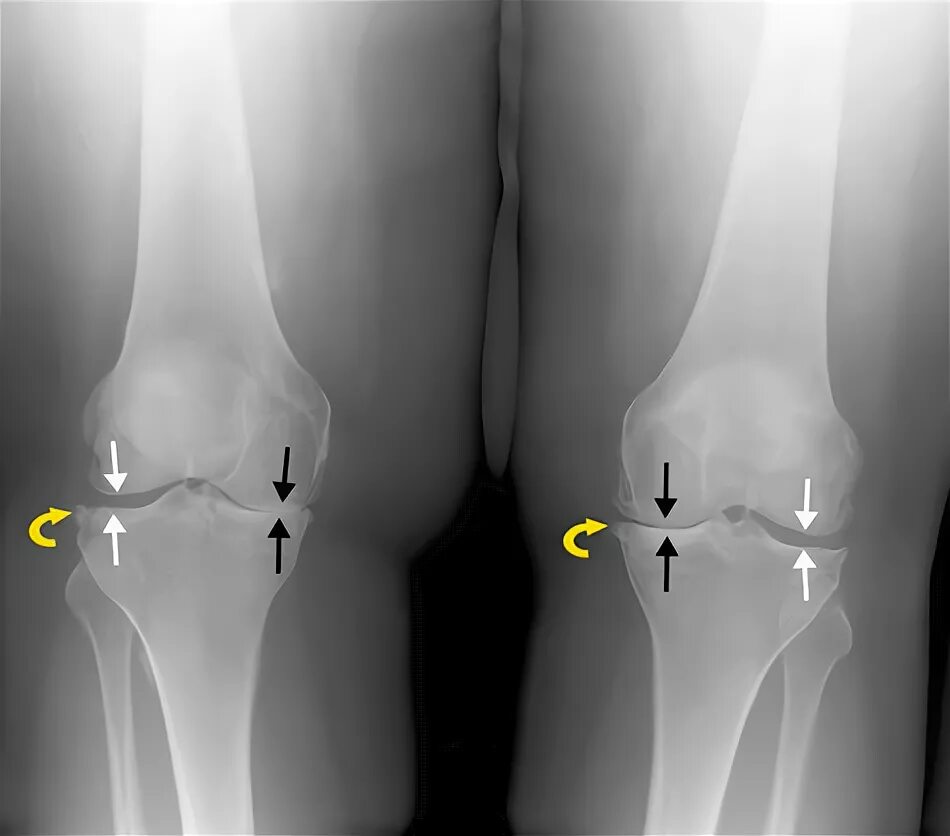

Гонартроз мрт